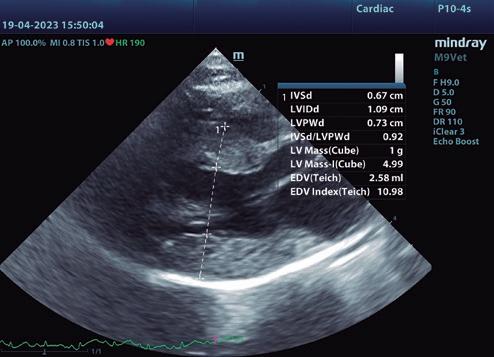

• Modo B: en la proyección paraesternal derecha eje largo, se observó un jet de regurgitación mitral con dirección posterior y SAM (figura 3). En el eje corto derecho a la altura de la base cardiaca se observó un ratio atrio izquierdo/aorta (AI/Ao) de 1,92 (>1,6 se considera dilatación AI) (figura 4). Además, se observó hipertrofia de la pared del septo interventricular (SIV) de 7,6 mm y la pared libre del ventrículo izquierdo (PLVI) la 8,4 mm (hipertrofia >6 mm) (figura 5).

• Modo M: en paraesternal derecho eje corto a nivel de músculos papilares se observó un aumento del grosor del SIV en sístole (SIVs) de 7,8 mm (hipertrofia >6 mm), así como una hipertrofia de los músculos papilares (figura 6). • Modo Doppler: en la proyección paraesternal izquierda apical cuatro cámaras se midieron los flujos mitral (onda E 0,89 m/s y onda A 0,66 m/s) y subaórtico (4,56 m/s) (figura 7) ambos turbulentos, pero con velocidades dentro de rango. Presencia de ODTSVI. El flujo dentro de la aurícula izquierda estaba ligeramente disminuido (0,23 m/s, rango <0.25 m/s), aunque sin smoke

Para el diagnóstico de fenotipo hipertrófico, la gold estándar es la ecocardiografía. Aunque no hay una medida mundialmente aceptada para un valor normal o anormal de grosor de la pared, un aumento focal o difuso por encima de 6 mm (Fuentes et al. 2020) confirma el diagnóstico. Un AI/ Ao >1,6, justifica la presencia de ICC. En nuestro caso, el diagnóstico de fenotipo hipertrófico, se sustenta por el aumento del grosor de la pared del VI (7,6 mm en modo B y 7,8 mm en modo M) y la ICC, por el del AI/Ao (1,92).